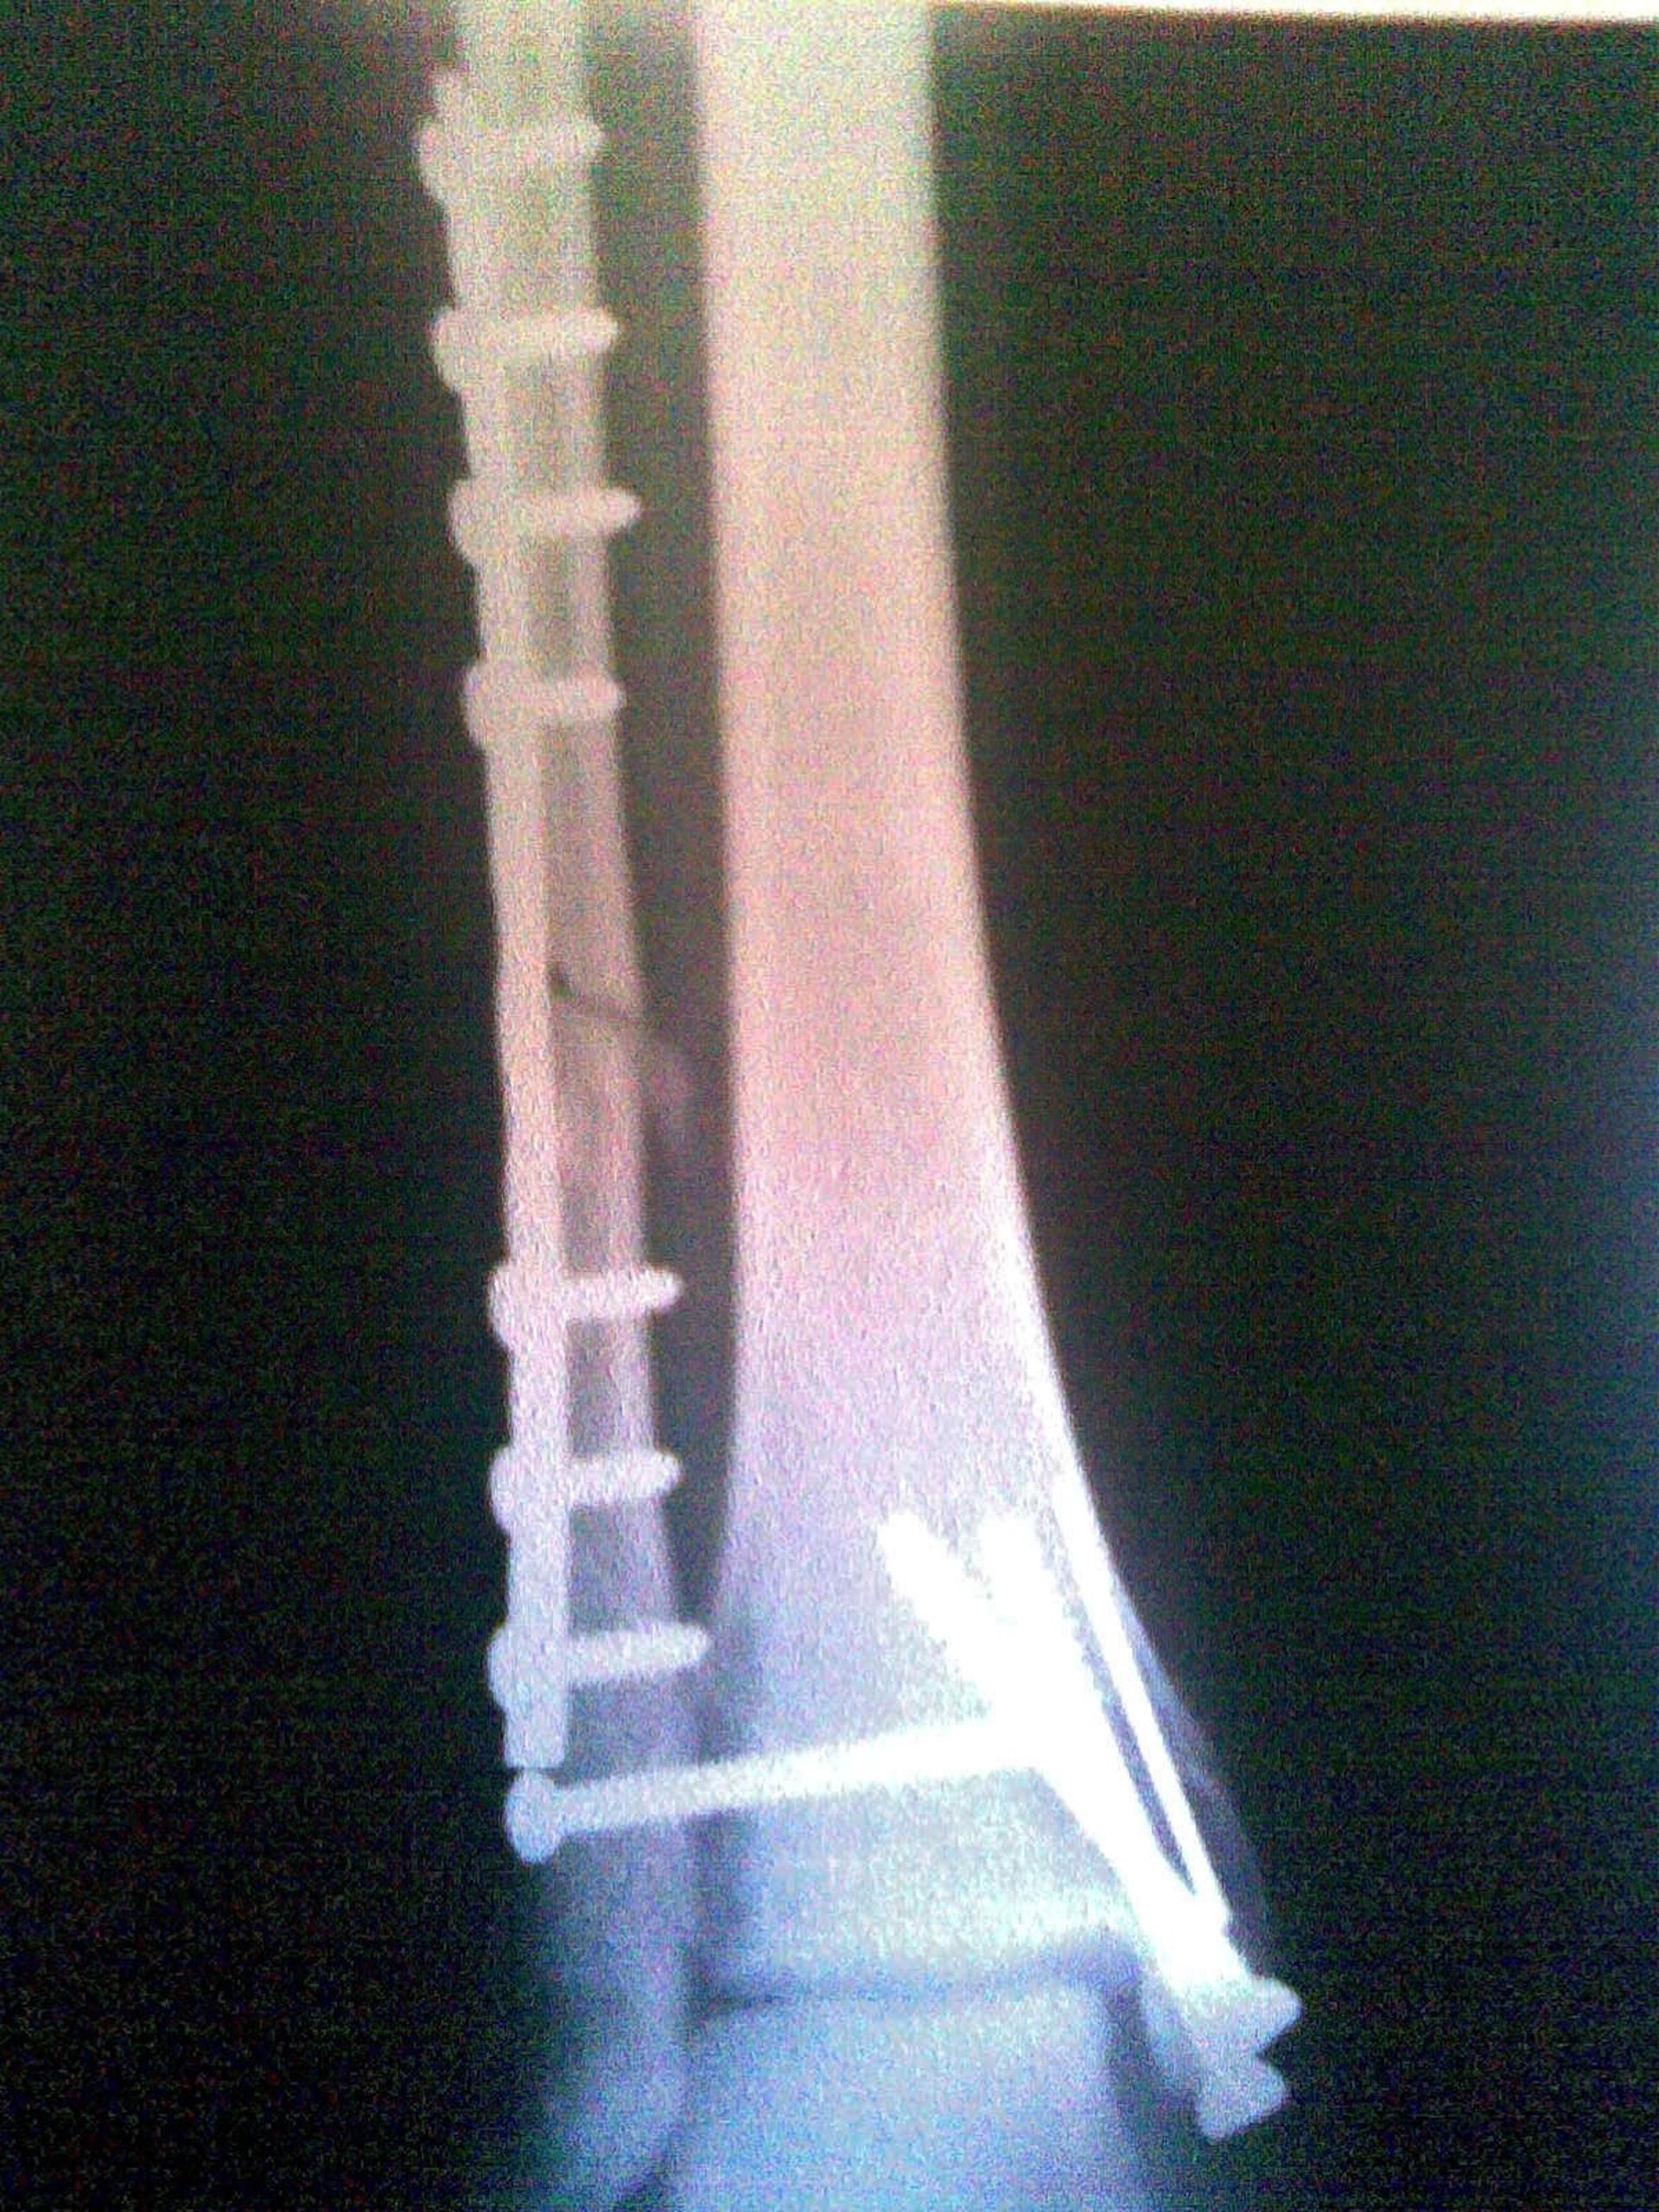

Radiografia, Hueso